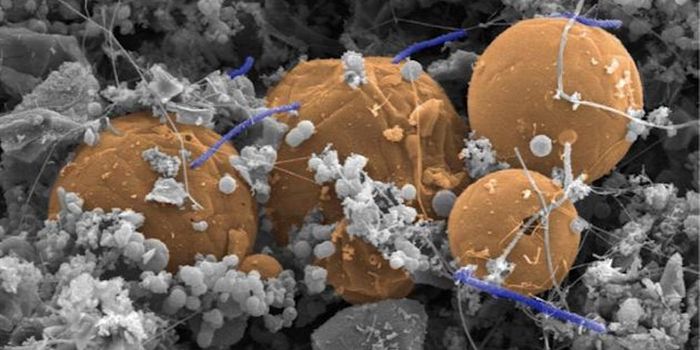

OCT 30, 2015MicrobiologyStaphylococcus aureus is notorious for forming biofilms on indwelling medical devices (things like urinary and vascular ...

JUL 09, 2015MicrobiologyBiofilms consist of surface-associated bacteria surrounded by an extracellular matrix (think dental plaque). Biofilms of ...

MAY 26, 2016MicrobiologyScientists have long searched for the answer to the question of how bacteria decide to cease normal function and form a ...